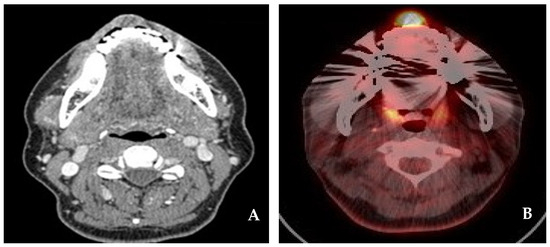

2.2. Case 2